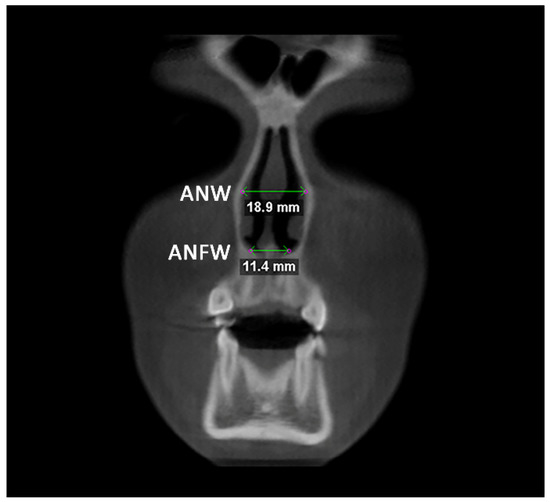

Afterward, the transverse dimension of the Apertura Piriformis was measured in the anterior and posterior regions. In the coronal plane passing through the cephalometric point N, the linear measurements of anterior nasal width (ANW) and anterior nasal floor width (ANFW) were performed (Figure 3, Table 1). Similarly, in the coronal plane passing through the upper margin of the mesial aspect of the Sella Turcica, the linear measurements of the posterior nasal width (PNW) and posterior nasal floor width (PNFW) were performed (Figure 4, Table 1). The entire procedure for skeletal measurements was performed by using the Dolphin 3D software (Dolphin Imaging, version 11.0, Chatsworth, CA, USA).

Figure 3.

Linear measurements of anterior nasal width (ANW) and anterior nasal floor width (ANFW) in the coronal plane.

In both TB and BB groups, there was a statistically significant expansion of the Apertura piriformis (ANW and ANFW) between T0 and T1 (p < 0.05), instead no differences were found between T1 and T2 (p > 0.05), thus maintaining the post-retention changes (Table 3). The expansion of the Apertura piriformis was significantly greater in the BB group compared to the TB group (TB) (p < 0.05) at each time point. The same findings were recorded for the PNW and PNFW measurements (Table 4).

4.1. Post-Retention Transverse Changes

Concerning skeletal measurements, the BB group showed a greater skeletal expansion compared to the TB group, which was consistent with previous findings [8]. The TB group showed a greater expansion of the pyriform aperture width compared to the posterior region confirming the wedge-shaped opening of the suture [4]; instead, BB groups showed a more parallel sutural opening [21]. Furthermore, both groups showed a cranio-caudal pattern of expansion (T0/T1 TB: ANW = 1.12 mm, ANFW = 1.61 mm; T0/T1 BB: ANW = 2.01 mm, ANFW = 2.66 mm), confirming the “V” shape opening of the mid-palatal suture [26]. It should be mentioned that subjects in the BB group were slightly older than those included in the TB group (<1 year); thus, they could present an advanced maturational stage of the mid-palatal suture that would have increased the skeletal resistances compared to TB group [27].